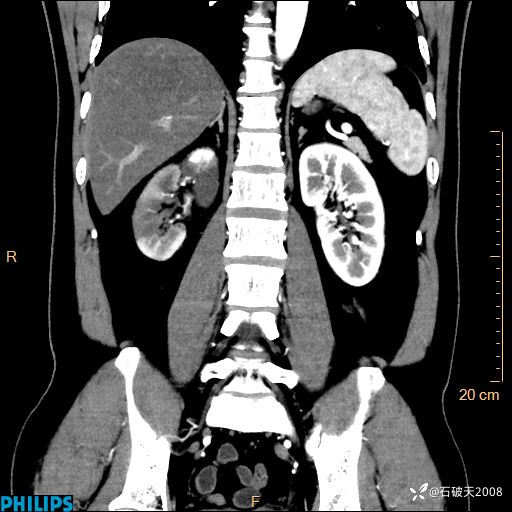

这个病例诠释了“腹部不增强,等于耍流氓”

MIP